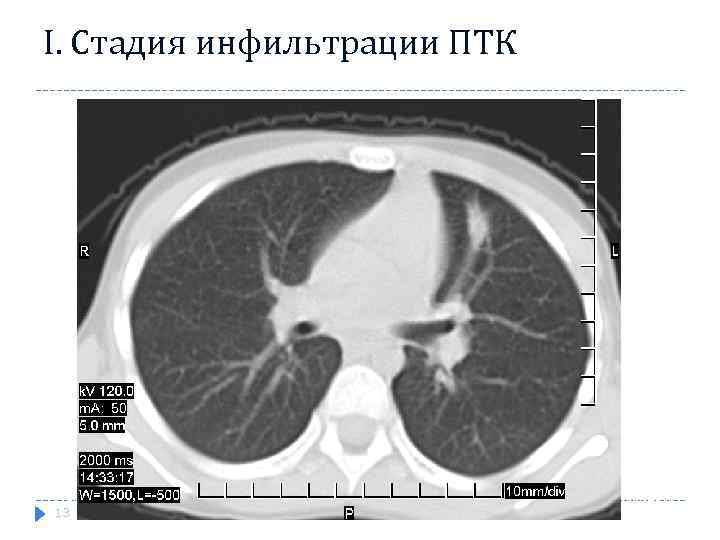

Рентгенологические признаки стадии инфильтрации ПТК Очаг или фокусное образование неправильной формы, с размытыми контурами и неоднородной структурой. Центральная часть затемнения, обусловленная первичным лёгочным поражением, имеет на рентгенограмме большую интенсивность, а окружающая перифокальная инфильтрация - меньшую. На стороне поражения отмечается также расширением и деформацией тени корня лёгкого с размытой наружной границей.

Рентгенологические признаки стадии инфильтрации ПТК Очаг или фокусное образование неправильной формы, с размытыми контурами и неоднородной структурой. Центральная часть затемнения, обусловленная первичным лёгочным поражением, имеет на рентгенограмме большую интенсивность, а окружающая перифокальная инфильтрация - меньшую. На стороне поражения отмечается также расширением и деформацией тени корня лёгкого с размытой наружной границей.

I. Стадия инфильтрации ПТК Характеризуется наличием одиночной гомогенной тени сливающееся с расширенным корнем легкого 13

I. Стадия инфильтрации ПТК Характеризуется наличием одиночной гомогенной тени сливающееся с расширенным корнем легкого 13